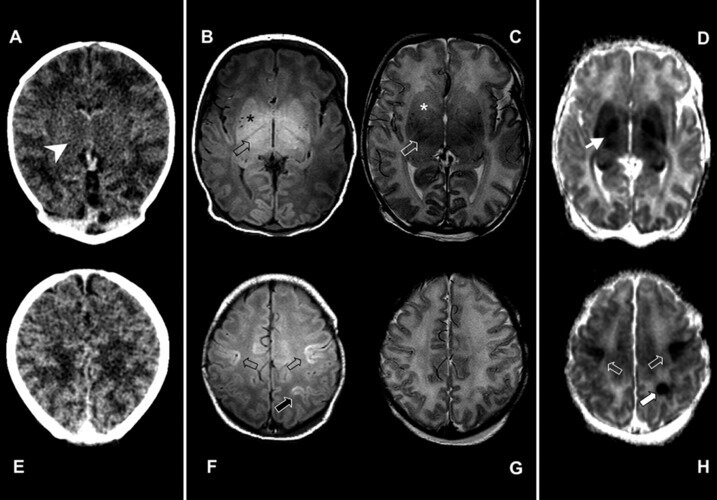

Что касается МРТ - опухоли мягких тканей при этом исследование видны уже сразу достаточно хорошо (и доброкачественные, и злокачественные). Особенно приоритетом этот метод должен становится при обследовании тканей головного мозга, в том числе, в диагностике опухолей. На КТ лучше видны кости черепа, и если подозрение на патологию в них, или вы обследуете опухоль и нужно уточнить прорастание, скажем, в кости - выбирайте тогда точно КТ (лучше сразу с контрастом). А вот если нужно посмотреть всё, что внутри той же черепной коробки - выбор за МРТ.

С головным мозгом мы выяснили: если смотрим внутри (опухоли, отёк головного мозга, рассеянный склероз, аневризы, инсульт и т.д.) - нужно МРТ, если кости черепа - то КТ.